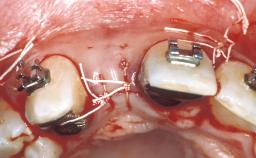

In September 2004, a 38-year-old female patient, a nonsmoker, was referred to our clinic for the replacement of the missing left central maxillary incisor (tooth 21),which had been removed two months before the initial appointment due to a vertical root fracture. The dental patient history revealed that the tooth in question had supported a ceramo-metal crown for more than ten years before the root fracture occurred. Implant therapy (single-tooth replacement) was considered the first therapeutic choice, as the neighboring teeth did not require significant restoration. The patient was in good general health, and her medical history revealed no significant findings.